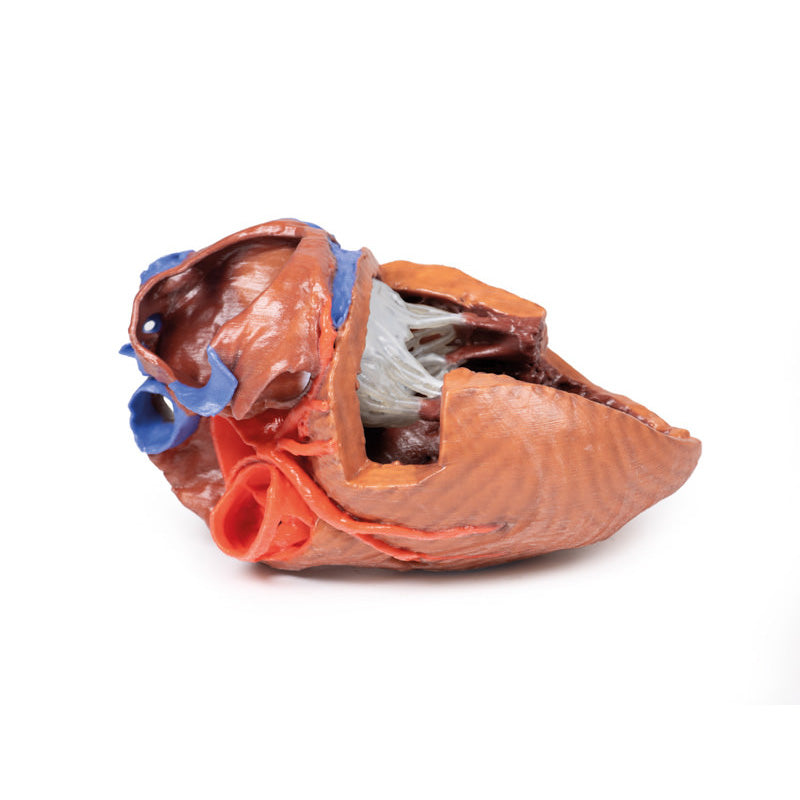

On the posterior side of heart the terminations of the pulmonary veins are visible entering the opened left atrium. Just anterior to the depression of the fossa ovalis in the interatrial septum the left atrioventricular valve with its two cusps (anterior and posterior) is preserved, along with the associated chordae tendineae and papillary muscles in the ventricle.

The walls of the opened left ventricle preserve well-developed trabeculae carneae. At the apex of the ventricle the aortic semilunar valve (with left, right, and posterior cusps preserved) can be seen at the base of the sectioned aorta alongside the origin of both coronary arteries. The left coronary artery in this specimen is very short, giving rise almost immediately from its origin to the left anterior descending artery, the diagonal artery, the ramus intermedius, and the circumflex branch. The latter branch passes between the left atrium and ventricle adjacent to the opened coronary sinus leading to the right atrium. The left anterior descending branch penetrates the myocardium in this individual and travels through the tissue, only emerging superficially to become visible again near the apex.

On the posterior side of heart the terminations of the pulmonary veins are visible entering the opened left atrium. Just anterior to the depression of the fossa ovalis in the interatrial septum the left atrioventricular valve with its two cusps (anterior and posterior) is preserved, along with the associated chordae tendineae and papillary muscles in the ventricle.

The walls of the opened left ventricle preserve well-developed trabeculae carneae. At the apex of the ventricle the aortic semilunar valve (with left, right, and posterior cusps preserved) can be seen at the base of the sectioned aorta alongside the origin of both coronary arteries. The left coronary artery in this specimen is very short, giving rise almost immediately from its origin to the left anterior descending artery, the diagonal artery, the ramus intermedius, and the circumflex branch. The latter branch passes between the left atrium and ventricle adjacent to the opened coronary sinus leading to the right atrium. The left anterior descending branch penetrates the myocardium in this individual and travels through the tissue, only emerging superficially to become visible again near the apex.